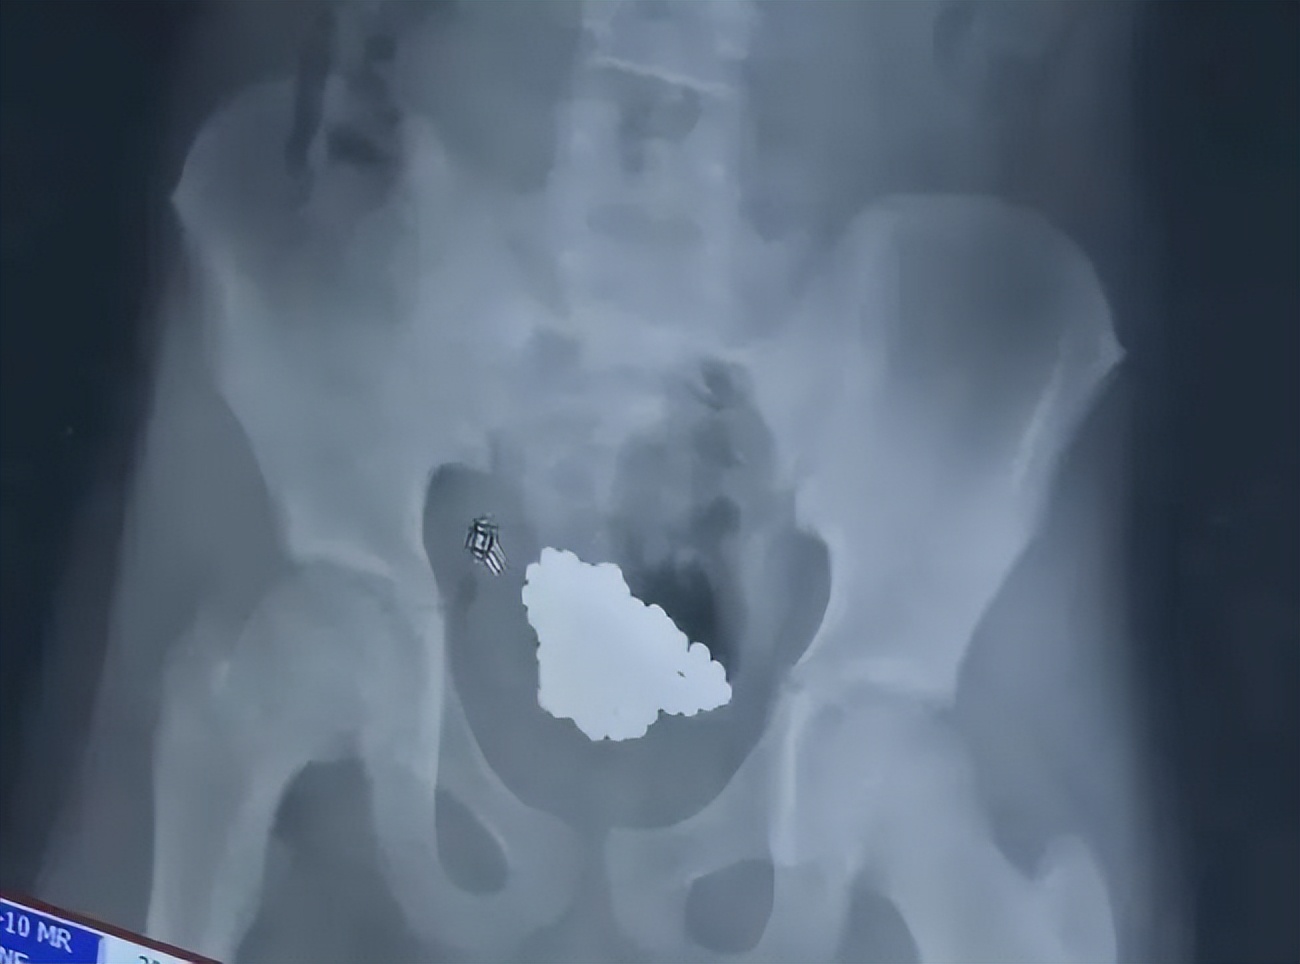

深圳一名13岁男孩,出于好奇往尿道里塞进186颗磁力球!

结果拍完片一看,医生都吓一大跳,孩子的膀胱里密密麻麻地全是磁力球。

这些磁力球全都粘在一起,根本排不出去,医生只能通过微创手术,将磁力球一颗一颗夹出来。